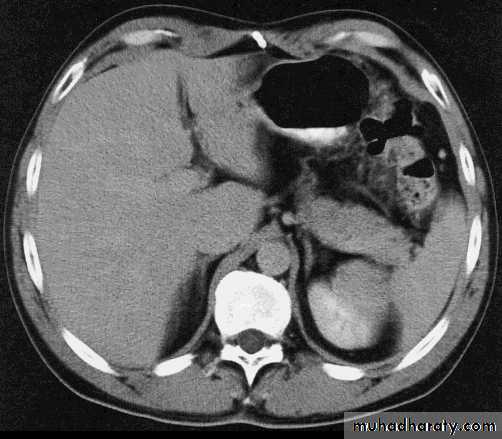

Comparisons

Cross sectionCAT image

abdomen

Computerized Axial Tomography (CAT)Sections are visualized as if you were looking at cross sections from below with the right side to your left

right

leftliver

spleen

liver